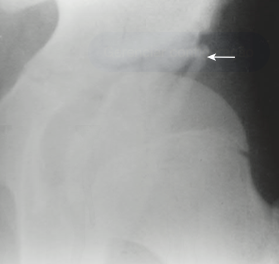

Principal alteração radiográfica

Achado radiográfico com obliquidade aumentada e perda da concavidade acetabular.

Q

Incluem redução inadequada, displasia residual do fêmur e do acetábulo, e necrose avascular da cabeça femoral.

Sinais radiográficos tardios

Desenvolvimento de osteoartrite e subluxação do quadril.